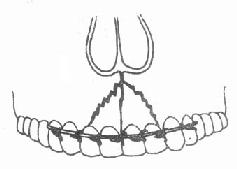

图4-11 牙槽突骨折和牙弓夹板结扎固定